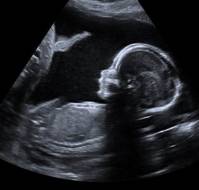

Fetuses with nuchal translucency measurements as low as 2.0 mm have a higher probability of chromosomal abnormalities, suggests a recent study published in JAMA Netw..

A recent observational study by Rema V Nair and colleagues evaluated the accuracy of nuchal translucency (NT) in detecting congenital heart defects (CHDs) at 11 to 1..